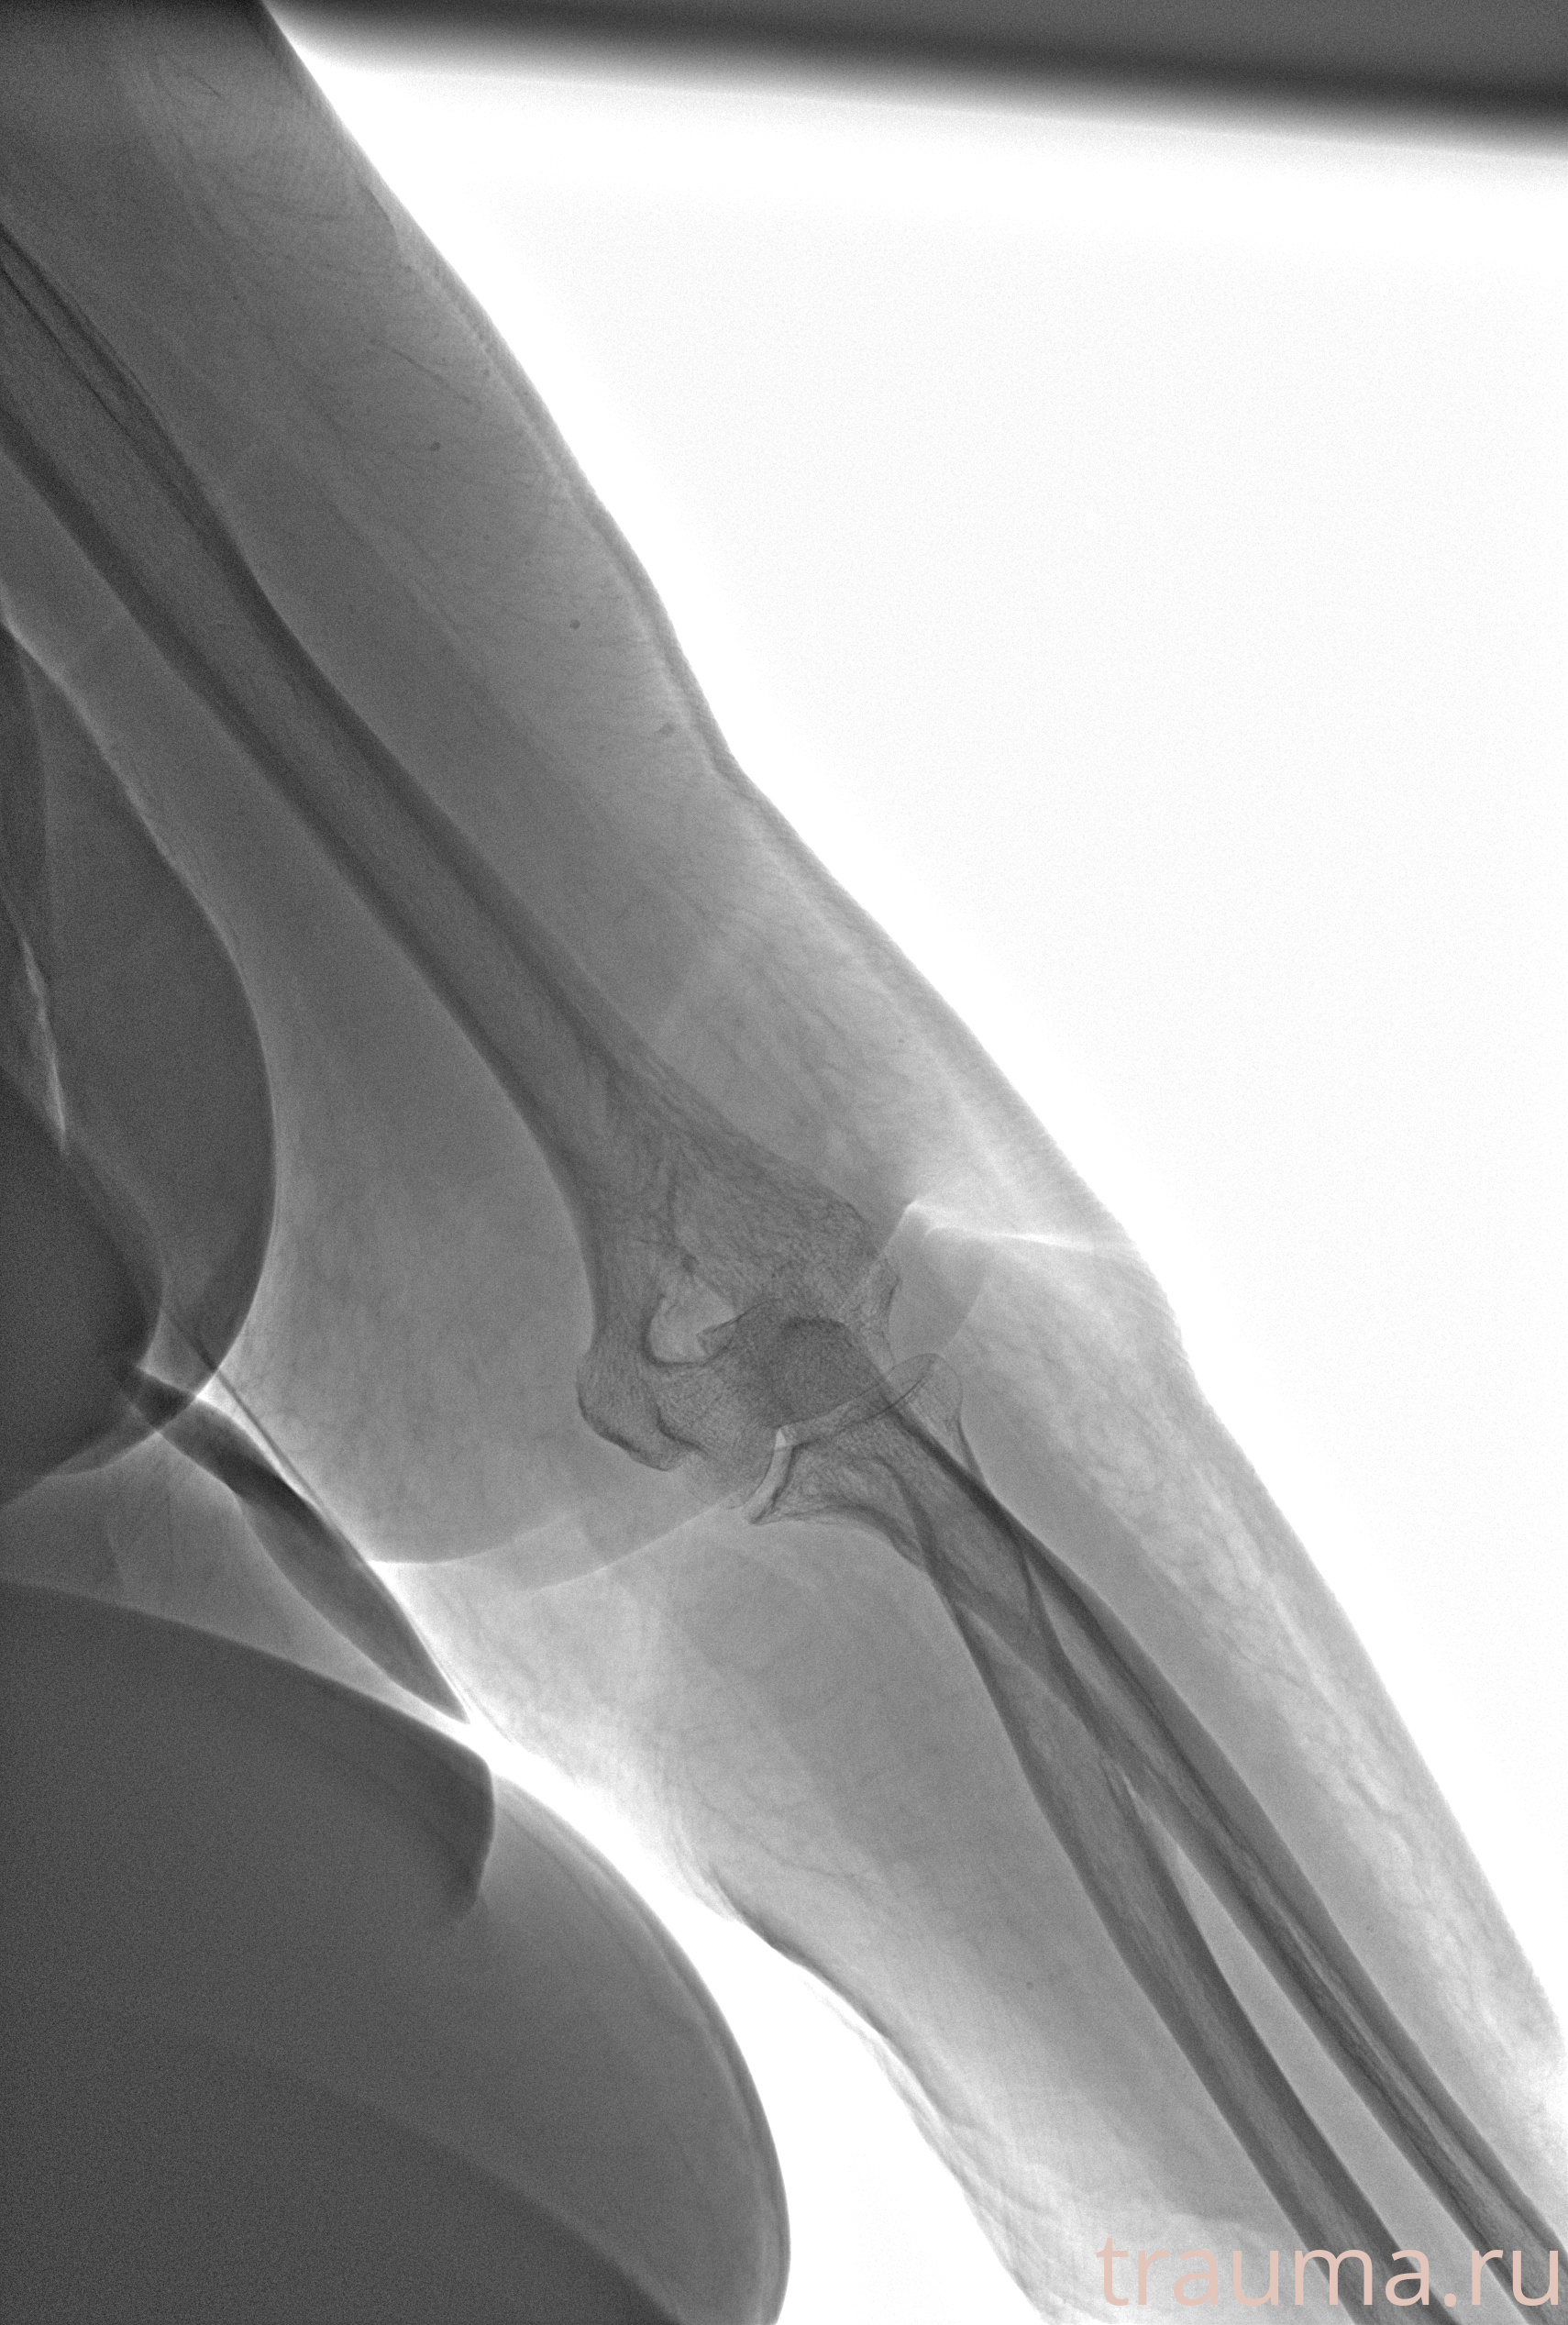

Рентгенограммы

Рентген на дому: по вашему адресу приезжает врач-рентгенолог, травматолог-ортопед с мобильным рентгеновским аппаратом, проводит диагностику травмы или заболевания, делает необходимые рентгенограммы, дает рекомендации по дальнейшему лечению. Получить качественные снимки в домашних условиях возможно благодаря уникальной методике, разработанной МосРентген Центром для института  Склифосовского